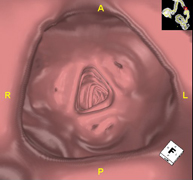

Prova diagnòstica no invasiva que consisteix en l'estudi de les artèries ilíaques i l'aorta abdominal a través de l'obtenció d'imatges d'alta definició anatòmica mitjançant l'ús d'un equip de TC (Tomografia Computeritzada) i de contrast iodat. La qualitat de les imatges permet realitzar reconstruccions en 2D i 3D gràcies a estacions de treball especialitzades en l'estudi arterial. Aquesta prova està especialment indicada com estudi prequirúrgic (mapa vascular) abans d'intervencions percutànies o quirúrgiques d'aorta abdominal, com l'estudi complementari en pacients amb isquèmia de membres inferiors, etc. - Colonoscòpia virtual

La colonoscòpia virtual és una tècnica no invasiva que permet la visualització tridimensional i bidimensional de l'intestí gros o del còlon mitjançant la presa seqüencial d'imatges captades amb TC Multidetector d'última generació. La qualitat de les imatges permet la navegació virtual per l'interior del recte i del còlon gràcies al processament en estacions de treball especialitzades. La preparació de la prova consisteix en realitzar una dieta baixa en fibra tres dies abans de la prova (per netejar el còlon i el recte) i de la ingesta de contrast oral iodat el dia abans de la prova (per marcar les femtes i poder distingir-les correctament de les possibles lesions colòniques). A diferència de la fibrocolonoscòpia, no requereix sedació ni solucions evacuants. La prova es realitza a la sala del TC, on, a través d'un petit tub flexible, s'insufla aire per distendre el còlon. - PAAF (Punció) Abdominal guiada per TC

L'Angio TC cardíac o la coronariografia no invasiva és una prova diagnòstica que consisteix en l'estudi de les artèries del cor o artèries coronàries mitjançant l'ús d'un equip de TC Multidetector d'última generació (64 corones o files de detectors) i de contrast iodat amb l'obtenció d'imatges bi i tridimensionals. El TC Multidetector 64 o TCMD64 permet una adquisició d'imatges tan ràpida que es poden valorar les artèries coronàries amb alta precisió anatòmica (estrenyiments o estenosis, calcificacions, variants anatòmiques, etc.), ja que, gràcies a la seva rapidesa, evita les falses imatges que provoca el moviment constant del cor (triga menys de deu segons en adquirir unes 1000 imatges). La informació obtinguda d'un tractament en estacions de treball amb programes especialitzats en la reconstrucció de les artèries coronàries que permeten valorar el nombre, la localització i les característiques de les lesions. Tota aquesta informació s'obté de manera no invasiva: només es necessita la punció d'una vena perifèrica (en el braç). És necessari que la freqüència cardíaca no superi els 75 batecs per minut, per això els pacients han de realitzar un tractament previ amb un fàrmac betabloquejant. - Angio TC d'aorta abdominal